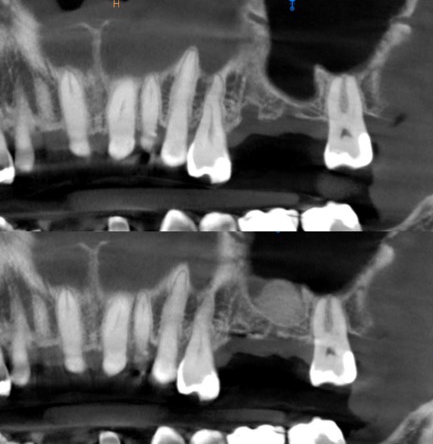

En effet, une reconstruction osseuse (Greffe osseuse) est indispensable, pour rétablir la hauteur ou la largeur de l’os maxillaire, avant ou en même temps que l’implantation. Ce sont soit les os du patient ou un substitut osseux qui sont utilisés comme matériau de comblement.

Il y a plusieurs techniques des reconstructions osseuses et une planification correcte nous donne la possibilité de choisir la technique la plus appropriée pour chaque situation.